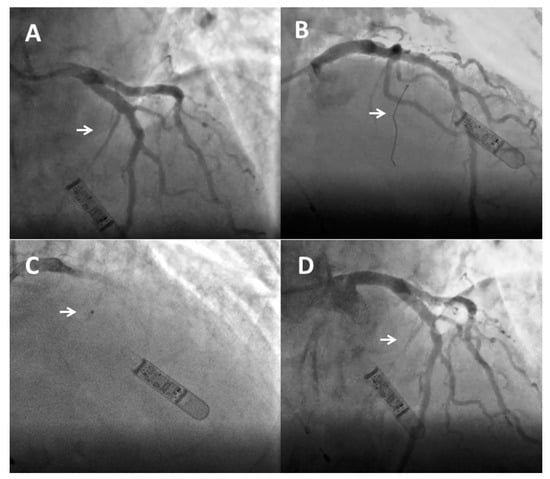

3.3. Description of the Procedure

3.4. How to Assess Procedural Success?